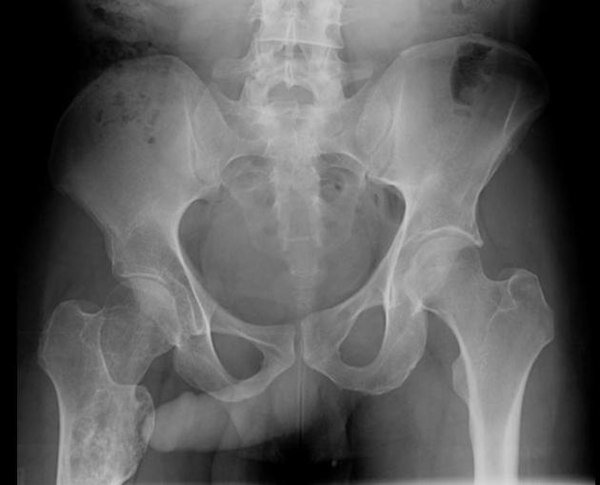

На представленном ниже снимке пенис указывает нам на опухоль (энхондрому) правой бедренной кости.

Энхондрома правой бедренной кости, и наш помощник чётко нам на неё указывает